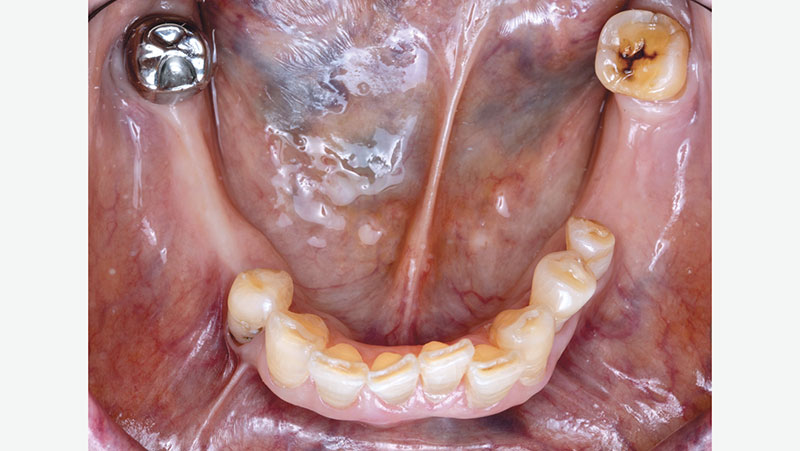

The Examination

For any new crown to fit properly under an existing appliance, the crown must conform to its clasps, rests and axial contours. It’s important to pay close attention to the fit of the existing appliance.

For existing partials, examine the occluding tooth contact, the position of the tongue, how the retentive and reciprocal arms are placed, and how it rests on the occlusal surface of the crown. Be sure to also examine the patient’s oral environment when the partial is removed, noting the spacing and the gingival region around the crown.

Original-crown-without-partial

Original crown without partial

Partial-over-original-crown

Partial over original crown

Occlusion-without-partial

Occlusion without partial

Ridge-spacing-without-partial

Ridge spacing without partial